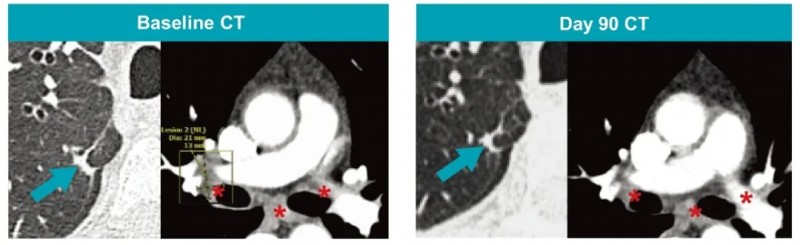

结果显示:在A2B694输注第90天,CT检查显示靶病灶全部消失(详见下图),达到RECIST1.1标准下的完全缓解(CR);第180天,经中央影像复核,正式确认这一完全缓解状态;第190天的PET-CT扫描未见疾病复发迹象。治疗后第6个月和第8个月,ctDNA检测结果持续显示KRAS G12V突变呈阴性,意味着肿瘤残留风险极低。

治疗期间仅出现一次特殊情况,在第243天患者出现孤立性脑转移,但颅外病灶仍维持完全缓解状态。针对这一情况,患者接受了地塞米松+根治性伽马刀放射外科手术联合,术后第284天复查PET-CT显示,病灶持续消失;直至治疗满12个月时,CT检查仍未发现新的病灶,疗效保持稳定。

▲图源“A2 BIO官网”,版权归原作者所有,如无意中侵犯了知识产权,请联系我们删除